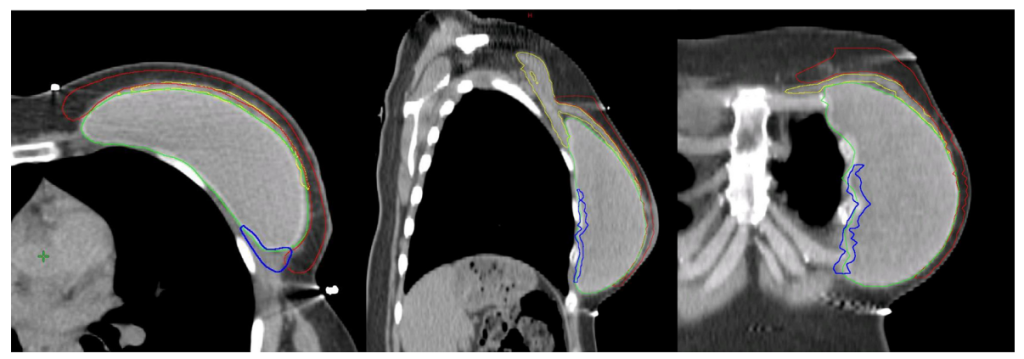

Hình 4b. CTVp_chestwall với phần trước (Đỏ) và sau (Xanh biển) trong trường hợp tổ chức bạch huyết dưới da cần được chiếu xạ cũng như phần thành ngực ban đầu không được bao phủ bởi cơ ngực lớn (Vàng). Túi độn sau cơ ngực (Xanh lá cây).

Với các bệnh nhân có yếu tố bất lợi và/hoặc nếu khối u nằm trong phần nhu mô tuyến sát mạc sau (Diện cắt tiệm cận, u nhuộm màu mực ở mạc sau tuyến vú) không được bao phủ bởi cơ ngực lớn (chủ yếu gặp ở các khối u phần thấp, thường nằm kết cận các xương sườn và cơ liên sườn), chỉ ngăn cách bởi mạc sau tuyến vú, chúng tôi khuyến cáo xác định thêm vùng tổ chức mô giữa thành ngực và túi độn ở phần thấp tính từ vị trí của cơ ngực lớn trước mổ (Lý tưởng nếu được đánh dấu bằng clip trong mổ), như một CTV phía sau tách biệt. (Hình 4B)